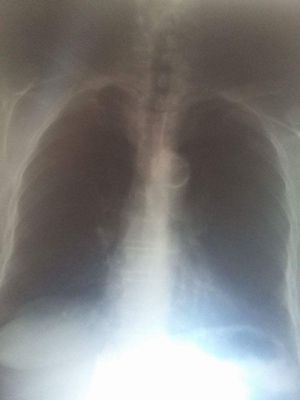

What do you think ?!,

an aged patient in an ordinary preanesthesia consultation !

Xray

Thorax

Interpretation

a better x-ray, this one is underexposed